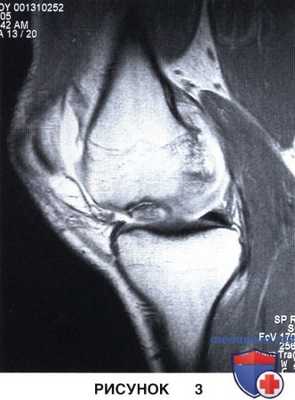

9. МРТ позволяет оценить размеры очага, целостность хрящевого покрова и подлежащей субхондральной кости, охарактеризовать поражение как стабильное или нестабильное:

• МР-признаки нестабильного поражения включают: (1) полоса высокоинтенсивного сигнала по периферии очага на Т2-взвешенных изображениях (рис. 3), (2) полоса высокоинтенсивного сигнала, проходящая через суставную поверхность, на Т2-взвешенных изображениях, (3) формирование субхондральных кист и (4) дефект суставной поверхности

• Чувствительность МРТ в отношении диагностики нестабильных РОХ у подростков и взрослых пациентов составляет 97-100%. Специфичность МРТ в отношении диагностики нестабильных очагов у взрослых пациентов также достаточно высока, тогда как у пациентов подросткового возраста она значительно ниже (11-15% согласно данным некоторых исследований). По сравнению с артроскопией МРТ обычно дает более высокую стадию заболевания и оценивает вероятность нестабильности фрагмента также как более высокую.